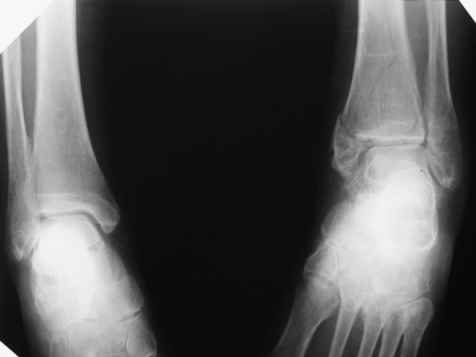

Посмотрели снимки после репозиции - не понравилась зона синдесмоза.

Сделали 3/4-е - впечатление, что в 99-том там что-то было. На

5.11.09г. запланирована КТ.

Косая после репозиции.JPG

79KB (81487 bytes)